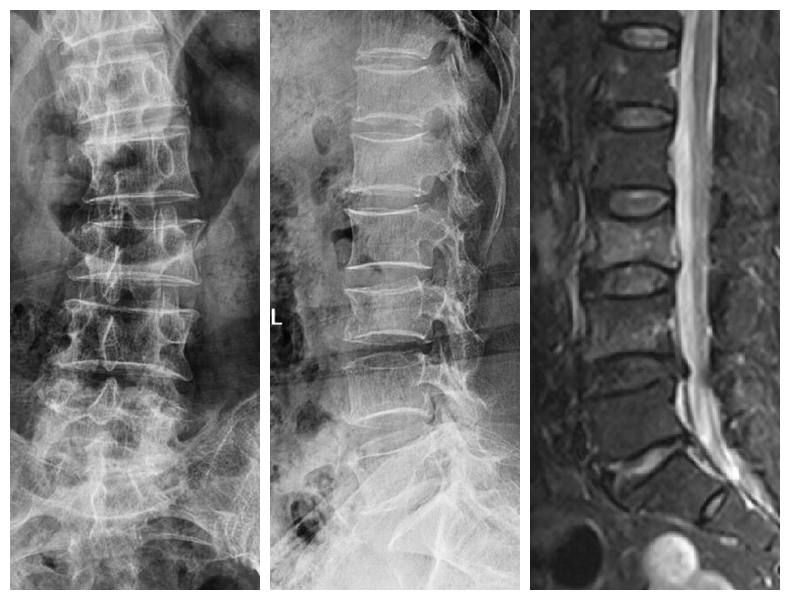

经皮胸腰椎骨折椎弓根螺钉内固定技术

传统胸腰椎骨折切开复位椎弓根螺钉内固定术组织创伤大、失血量大、住院时间长、下地时间晚、费用高。经皮胸腰椎骨折椎弓根螺钉内固定技术组织创伤小、失血少、住院时间段、下地时间早、费用低。

典型病例:患者**,男性,43岁,因“摔伤致胸腰背部疼痛、活动受限2小时”门诊平车入院。双下肢肌力、感觉及肌张力正常。

本例患者术后5天在腰围保护下独立下床,双下肢肌力感觉正常。